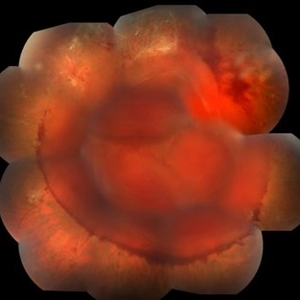

Syphilis Neuroretinopathy

Female patient, 21-years-old, with complaint of low vision in the right eye for 3 years. According to information from the patient's history, at the time she noticed the low vision, it also coincided with a picture of a strong urinary infection as well as episodes of constant tonsillitis. Yes, the patient did not seek medical attention and self-medicated with antibiotics. In ophthalmologic evaluation, as well as examinations of color retinography and ocular fundus autofluorescence, important pigmentary alterations were observed following vascular arches with pigment mobilization in osteoclasts (aspect of a unilateral pigmentary retinitis secondary to the inflammatory process). Which suggested inflammatory process sequelae. Through the laboratory tests, he had positive (+) confirmation for SYPHILIS NEURORETINOPATHY .

Photographer: JEFFERSON R SOUSA - Study Center and Ophthalmological Research Dr. Andre M V Gomes, Institute Dr. Suel Abujamra São Paulo-Brazil

Imaging device: Fundus camera Topcon TRC-50 DX, Imaginet 5.0, angle de 50 graus. Flash 36 / Mosaic with 10 images.

Condition/keywords: neurosyphilitic optic atrophy, retinitis pigmentosa, syphilis, syphilis neuroretinopathy